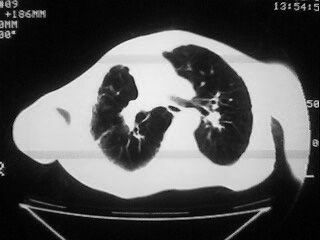

m,45,咳嗽、气憋月余。先天性畸形

1)两肺上叶继发性肺结核,部分肺间质纤维化。2)慢性支气管炎。3)肺气肿,两上肺多发性肺大泡。4)右侧胸膜增厚可能。5)脊柱上胸段畸形。

肺间质纤维化、肺大泡

两上肺结核、纤维化,两上肺肺大泡,

考虑:1)两肺上叶继发性肺结核,部分肺间质纤维化。2)慢支肺气肿并两上肺多发性肺大泡。3)右侧胸膜增厚可能。5)脊柱上胸段畸形。

补充一下,病人有强直性脊柱炎十多年